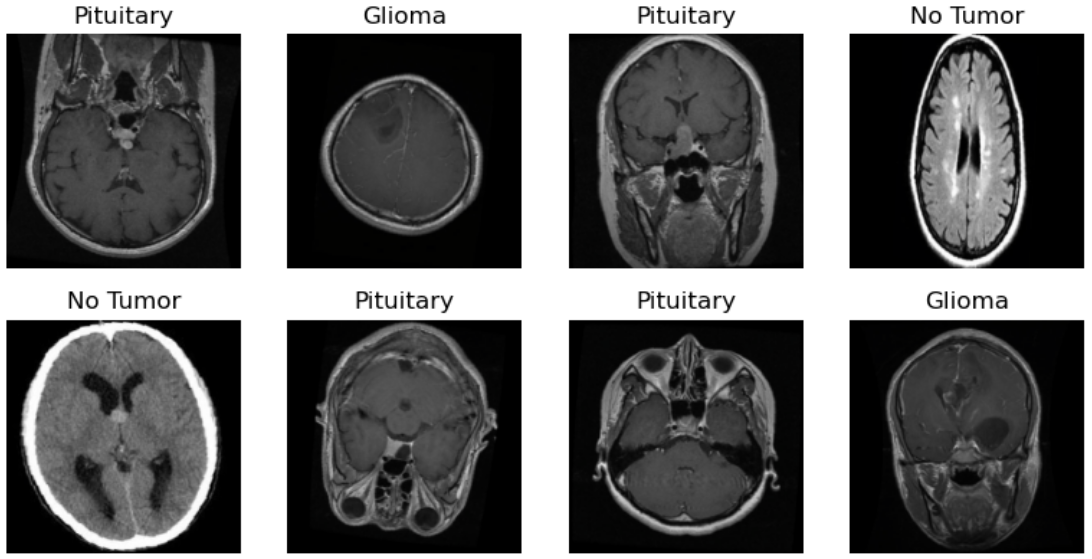

Brain Tumor Detection Based on MRI Images and Artificial Intelligence

Brain tumors, as central nervous system diseases that endanger human health , require early and accurate detection to significantly improve patient survival rates. Magnetic Resonance Imaging (MRI), due to its superior soft-tissue contrast and non-invasiveness, has become a crucial tool in brain tumor diagnosis. However, traditional imaging diagnosis, which heavily relies on manual interpretation, suffers from limitations such as strong subjectivity and low efficiency. To address these issues, this paper proposes an automatic brain tumor detection method based on Convolutional Neural Networks (CNN). By leveraging deep learning techniques, the method extracts multi-level features from MRI images to achieve high-precision classification of glioma, meningioma, pituitary tumor, and non-tumor categories. A lightweight CNN model was developed, incorporating data augmentation and normalization preprocessing strategies. Experiments were conducted on a dataset of 7,023 MRI images. The results show that the model achieved classification accuracies of 96% on the training set and 95% on the validation set, demonstrating strong robustness and generalization capability. Confusion matrix analysis indicates that the model maintains high recognition accuracy across all categories, with particularly outstanding performance in identifying non-tumor and pituitary tumor cases. This study provides an effective technical pathway for intelligent assisted diagnosis of brain tumors and holds promising clinical application potential.